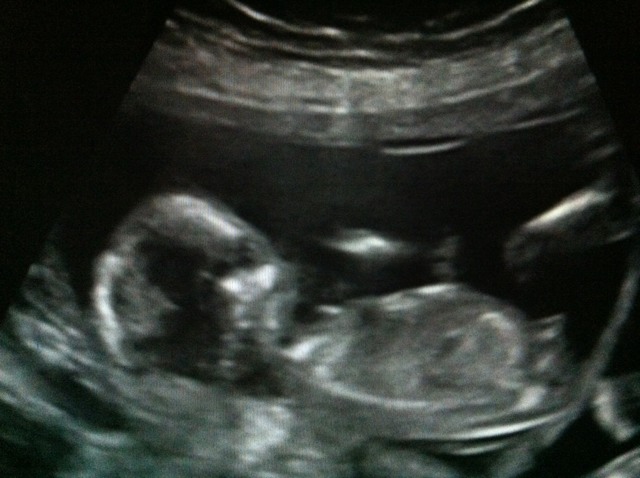

differing nubs, pics added

I had a scan at 13+6, twin 2 was measuring 13+5 & twin 1 was measuring 14+2

Twin 1 had a classic boy nub, a bump rising almost straight up clearly defined. He did have the cord between his legs for the whole scan though, this can't image as a bump though can it?

Twin 2 has a distinct nub sticking out at 13+6 would this have shrunk? When the sonographer was pointing out boy he said see this bump doesn't it look like boy but he was on a diagonal and almost a potty shot I think the nub though obvious was pointing out not up. We could clearly see the nub on the 3D looking like a little winky but I still think it wasn't angling up.

I just don't know Twin 1,'s nub is so classic I have no doubts but looking through the girl confirmed pics I can see lots of nubs that look like twin 2's and have been girls. When the full nub is not imaged it looks like a flat line but when the full nub is imaged it is distinctly sticking out and a bit up but is flat on top not a bump like twin 1's.